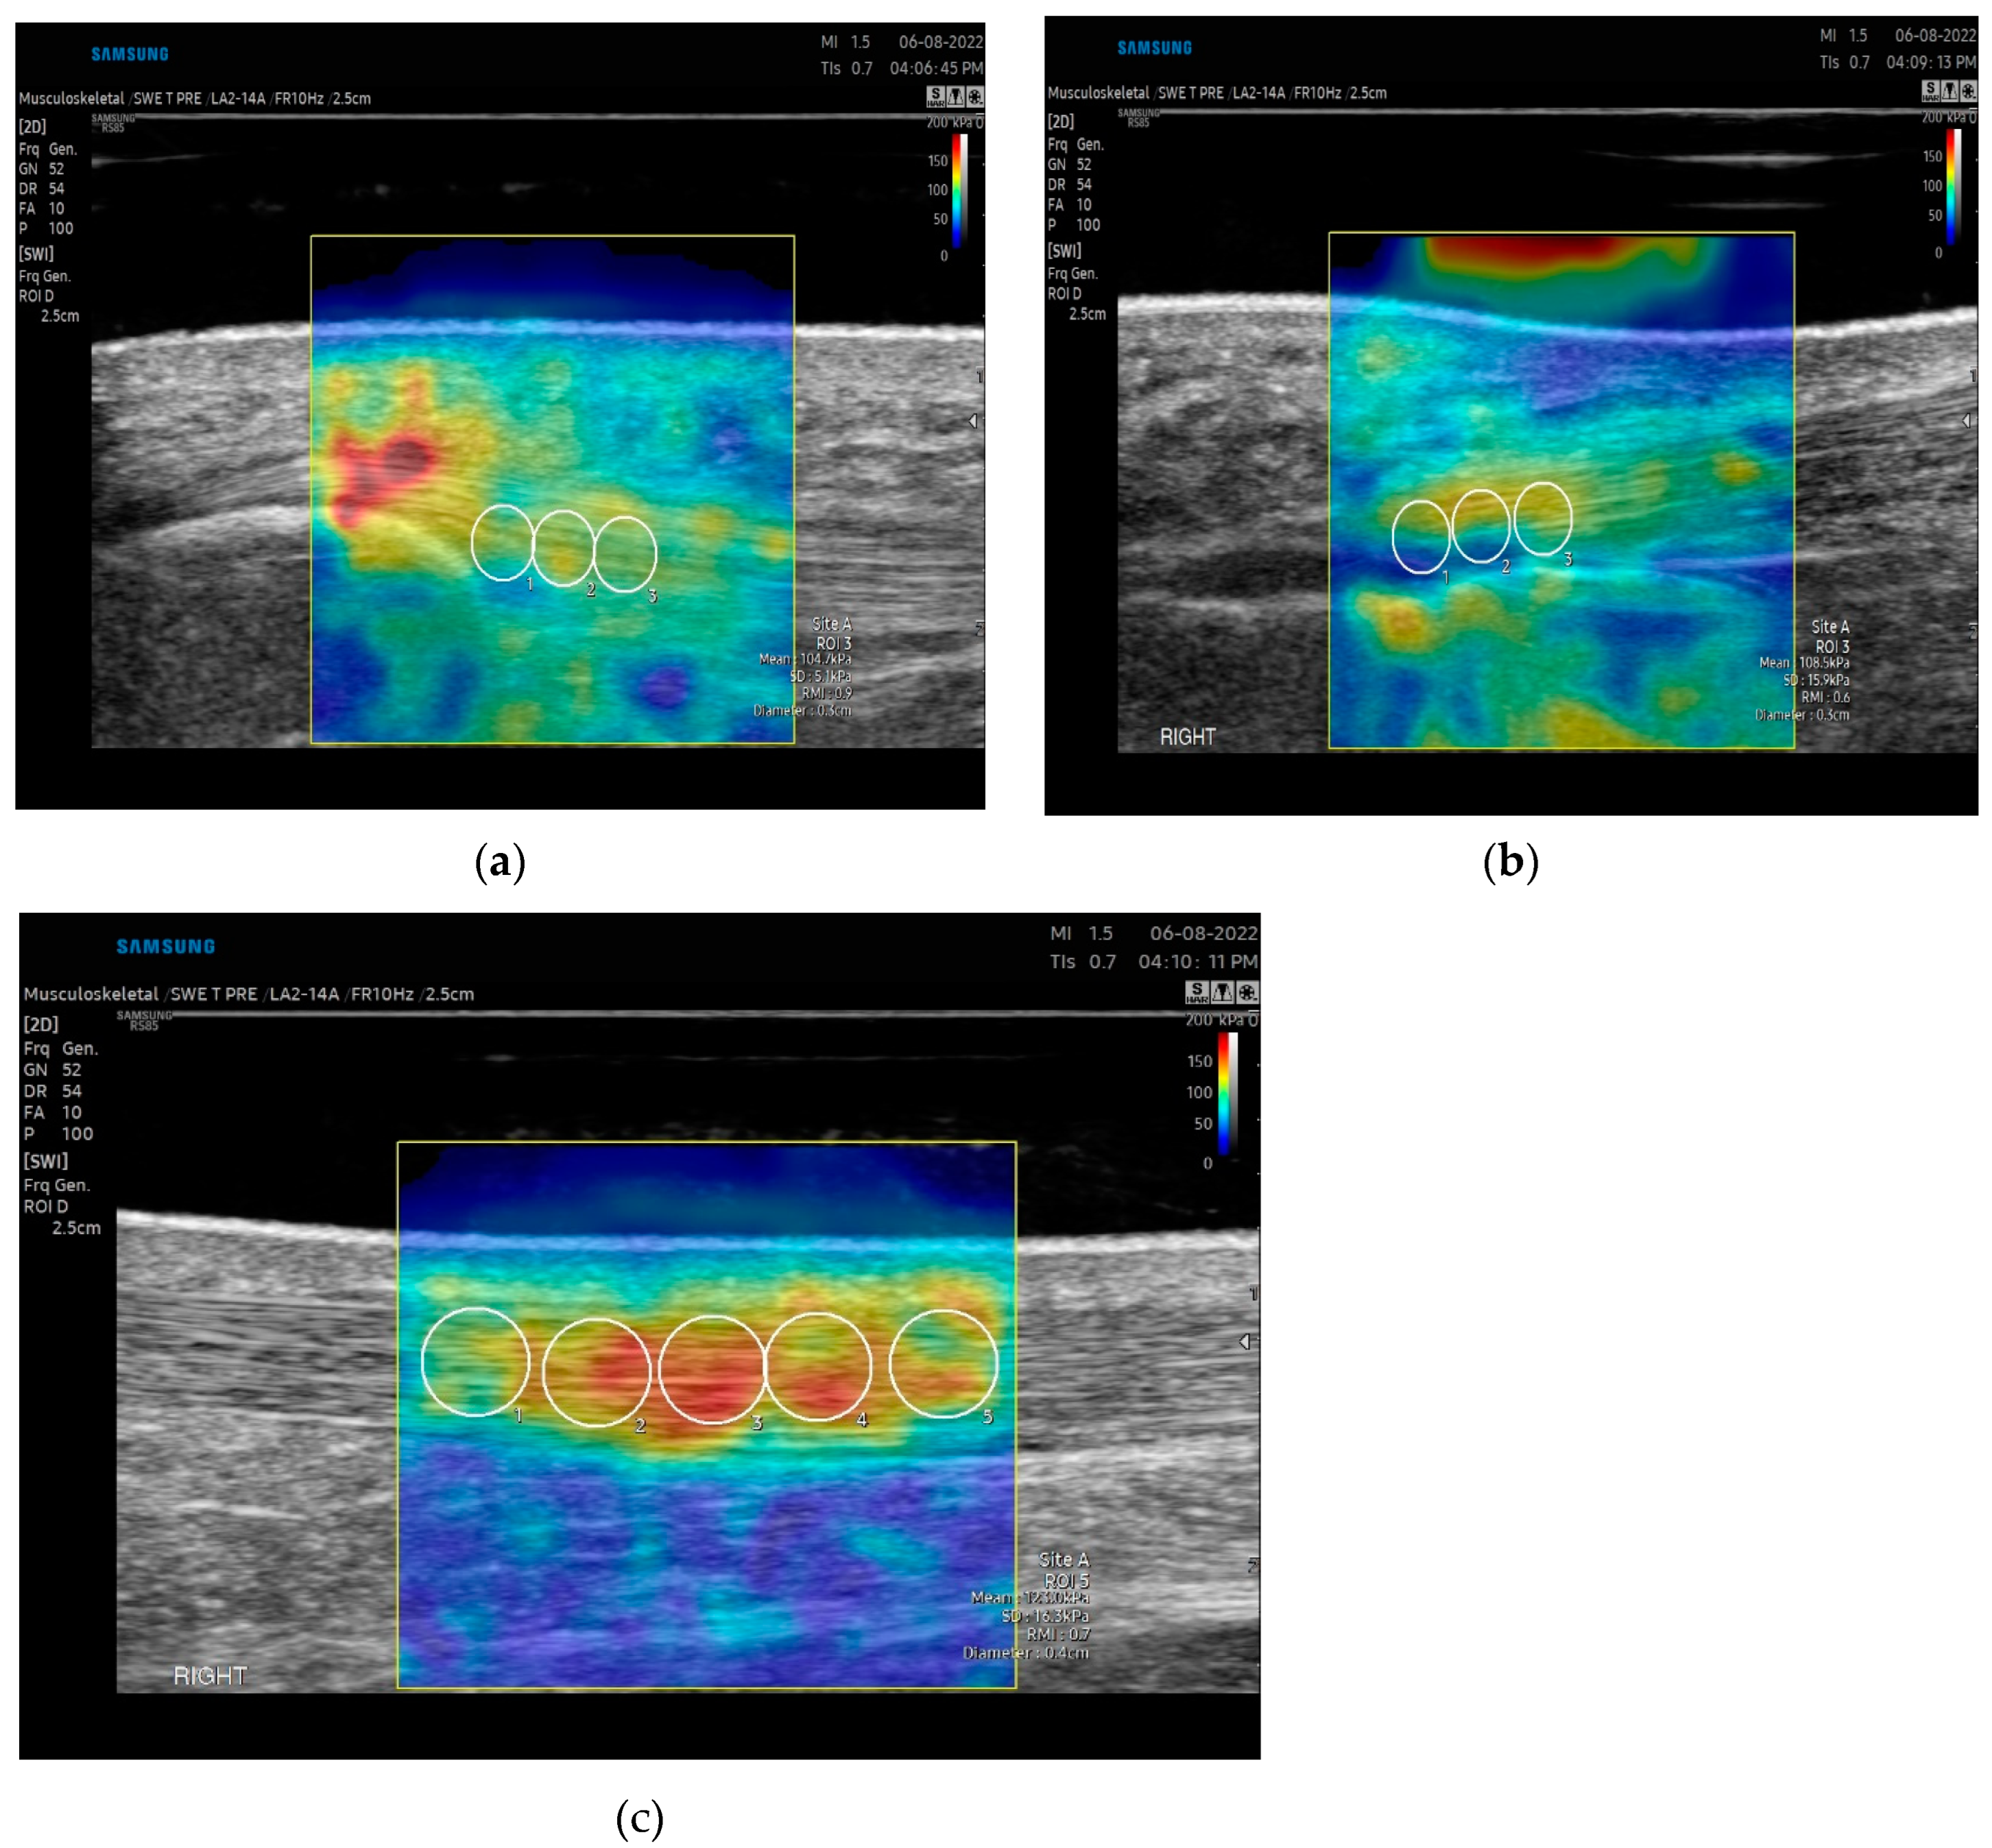

Image Acquisition: For the patellar tendon, participants were assessed supine with the knee flexed and supported at 30 degrees with the hip in a neutral position (Figure 1a). Approximately 5mm of ultrasound gel was applied using a gel standoff pad, and images were taken without significant pressure, given that pressure directly affects SWE measures[13]. The transducer was rotated into the long-axis position on the tendon. Five images were taken by the examiner to account for image artifact and reproducibility. The transducer was removed and again placed on the target tissue for each measurement. Data acquisition was obtained at the proximal portion of the patella tendon with initial measures at the peak of the lower apex of the patella. A 1.25 x 2.5cm rectangular box was used as the region of interest. A 3mm diameter q-Box was used for data analysis. Three adjacent measurements using the 3mm q-box were taken spanning from the proximal to the midportion of the patella tendon (Figure 2a). Average values, not maximum values, were reported, as maximum values fluctuate with ROI[13]. Images were only included if RMI (reliability of the measurement) was greater than 0.6 and IQR/Med (Interquartile/Median) ratio was under 30%. Outliers were removed if deemed an area of anisotropy based on the B mode acquired image.

For the achilles tendon, all participants were assessed in a prone position, with the knee fully extended and the foot relaxed overhanging the bed (Figure 1b). Relaxed positioning of the tendon has been shown to have the highest reliability in assessment[4]. Approximately 5mm of ultrasound gel was applied to maintain good contact between the ultrasound probe and skin without significant pressure using a gel standoff pad. The transducer was rotated in the long-axis position. Five images were taken by each examiner to account for image artifact and reproducibility. Data acquisition was performed at the insertion and midportion of the tendon (Figure 2b and 2c). The midportion of the achilles tendon was determined by identifying the thickest portion of the tendon proximal to the insertion (approximately 5cm from the calcaneus) and centering this midline with the transducer. A 1.25x 2.5 cm rectangular box was used as the region of interest. A 3mm and 4-5 diameter q-Box was used for data analysis of the insertional and midportion achilles respectively. Three measurements for the insertion and five measurements for the midportion were taken spanning the tendon and the length of the q-Box.

Figure 2. Longitudinal elastogram of (a) proximal patella tendon (b) insertional achilles and (c) midportion achilles tendon in a 39-year-old healthy male. The Q box is represented by the circles placed within the elastogram. The Q-box within the region of interest for the patella tendon and insertional achilles is 3mm and the midportion 5mm.